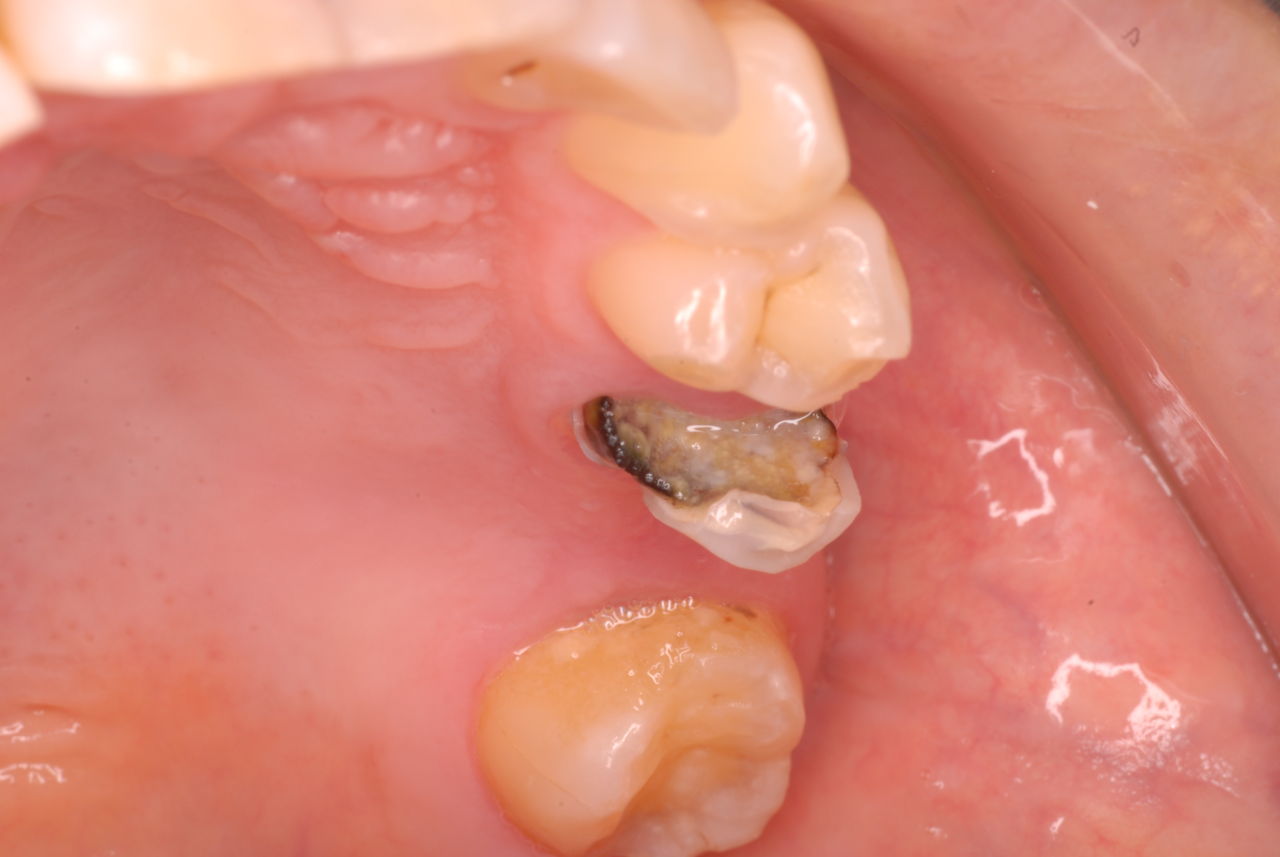

なかなかブラシの使い方ができていないようで、歯磨きと歯周病でのブラシの使い方は別なのですが、習ったことも検査もされずに金属を被せたりしているようで、これからも歯医者さんで抜かれたり、その後にインプラントのような高価な“クギ”を打ち込まれる方が増えるかと思うと残念です。

被せても、詰めても病気は治らないのですから。又病気の元になり易い不適合な差し歯や金属、インプラントがあればそこからバイキンが侵入して体に悪さもしやすいのではないかと心配しています。

歯周病と根尖病巣(根管内とは違う)の菌は同じだとか、所謂biofilm感染症なのだと。